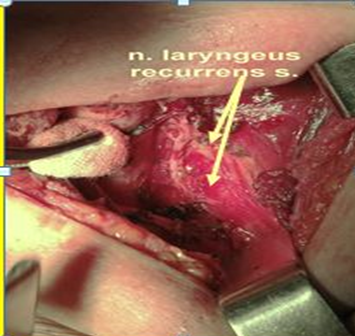

Пациент М., 54 г. Узлы в щитовидной железе выявлены при УЗИ в 2013 г. При контрольном УЗИ в 2015 г. отмечена отрицательная динамика в виде увеличения узла правой доли в размерах с 9 до 13 мм. В РНЦРР проведено комплексное обследование: произведена тонкоигольная аспирационная пункция, морфологически подтвержден папиллярный рак щитовидной железы. Регионарного и отдаленного метастазирования не выявлено. Также у пациента в анамнезе лечение по поводу рака левой молочной железы Т1N0М0: выполнена радикальная резекция левой молочной железы и проведена лучевая терапия. Непродолжительное время лечение антиэстрогенными препаратами. 13.10.2015 выполнена тиреоидэктомия с микрохирургическим невролизом возвратных гортанных нервов. Интраоперационно: при мобилизации выявлен правый невозвратный нижний гортанный нерв (вариант 2В). Выполнен невролиз правого ННГН: прослежен от правого блуждающего нерва на уровни гортани до впадения в гортань, сохранен (рис. 5).

Рис. 5. Интраоперационный вид. Белая стрелка – невозвратный нижний гортанный нерв.